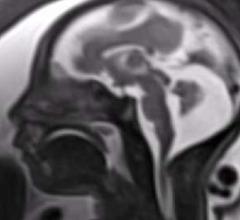

Patricia Oliveira-Szejnfeld, M.D., and Fernanda Tovar-Moll, M.D., Ph.D., explain what radiologists should be looking for ...